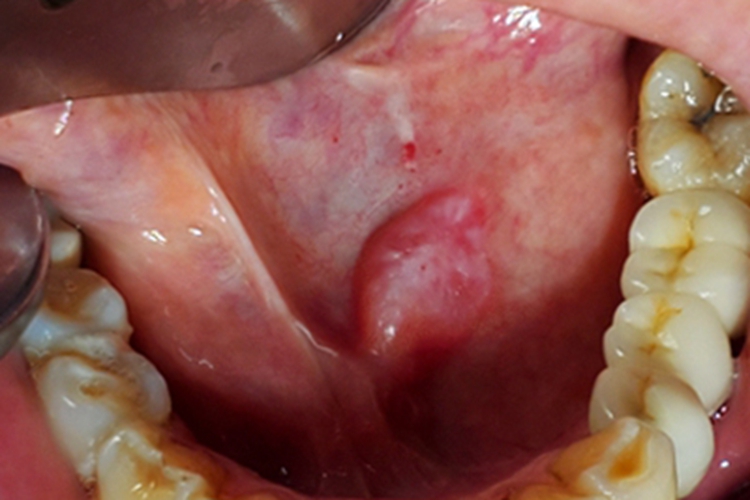

涎腺囊肿皮损可表现为疙瘩,如蚕豆大小,质地较软,表面光滑,有反光感,患者可自觉有异物感,局部可自发破溃,流蛋清样液体,常反复出现。

涎腺囊肿可发生在腮腺、颌下腺及舌下腺区,涎腺导管因炎症或结石阻塞使腺体分泌物潴留所致,阻塞原因多系损伤,有时多次反复损伤,可形成瘢痕而阻塞排泄管。